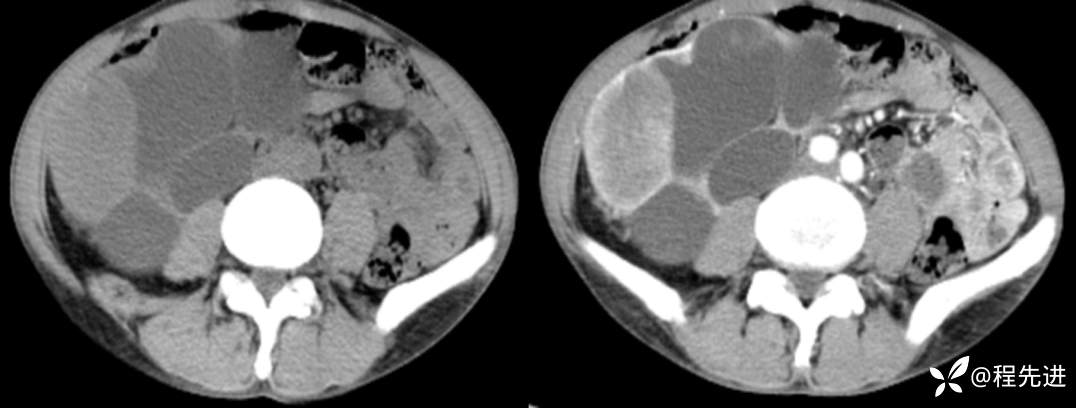

CT平扫+增强

左平扫,右增强